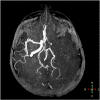

Case presentation: A 40-year old female patient with a four-day history of severe diarrhea presented with right hemiplegia and altered mental status. Imaging revealed left middle cerebral artery occlusion and left transverse and sigmoid venous sinus thrombosis, along with left jugular vein thrombosis. Her laboratory evaluation was notable for profound iron deficiency anemia, thrombocytosis, and hyperhomocysteinemia. Her positive anti-tissue transglutaminase IgA antibodies and ensuing duodenal biopsy confirmed the diagnosis of celiac disease.